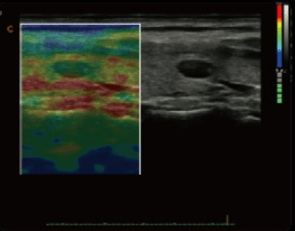

- Gracias a su tecnología de doppler continuo, CW, imágenes tisulares TDI, cálculos automáticos IMT, el modelo Cbit 6 permite una mayor flexibilidad y flujo de trabajo.